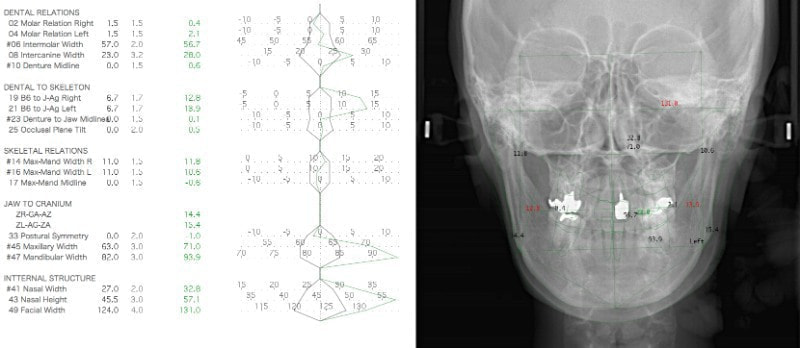

セファロ分析正貌

顔面の幅径はかなり狭い傾向にあります。

セファロ分析結果:上顎の劣成長と下顎の過成長が認められる値が出ています。重度の叢生といえます。